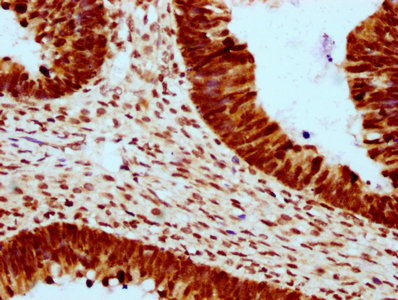

IHC image of CSB-PA010403OA23ncrHU diluted at 1:10 and staining in paraffin-embedded human ovarian cancer performed on a Leica BondTM system. After dewaxing and hydration, antigen retrieval was mediated by high pressure in a citrate buffer (pH 6.0). Section was blocked with 10% normal goat serum 30min at RT. Then primary antibody (1% BSA) was incubated at 4°C overnight. The primary is detected by a biotinylated secondary antibody and visualized using an HRP conjugated SP system.